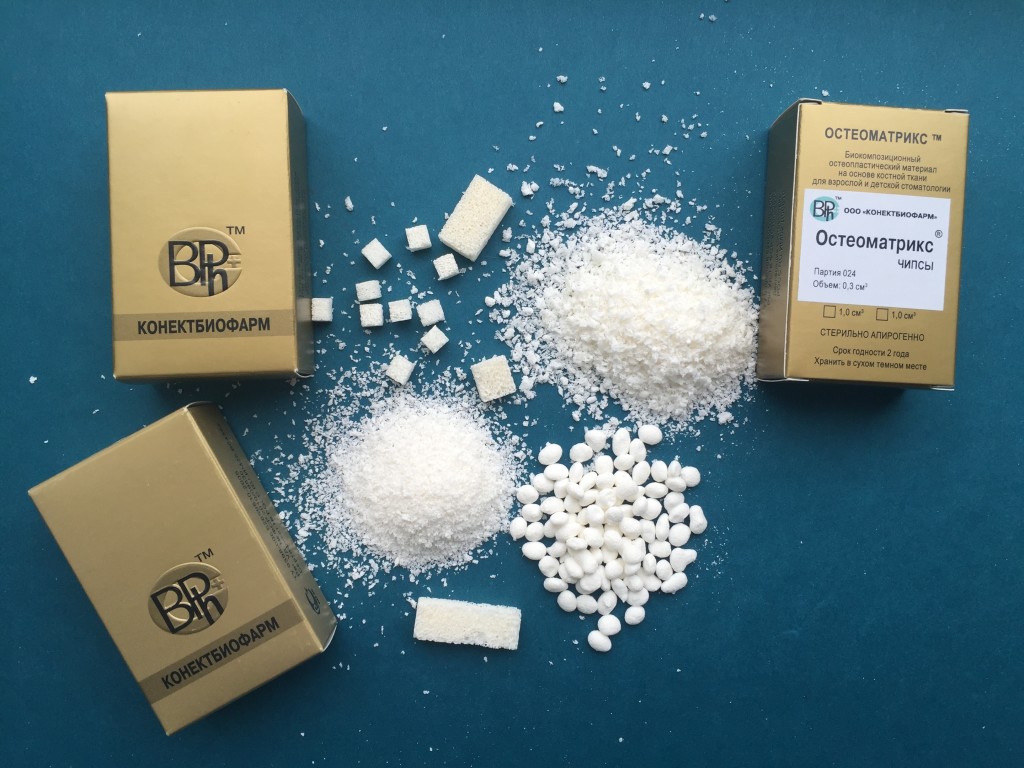

Далее мы рекомендуем укладывать Остеоматрикс в виде чипсов. Это остеоиндуктивный материал, который непосредственно участвует в стимуляции процессов костеобразования и в дальнейшем полностью замещается вновь образованной костью (рис 5).

Далее мы рекомендуем укладывать Остеоматрикс в виде чипсов. Это остеоиндуктивный материал, который непосредственно участвует в стимуляции процессов костеобразования и в дальнейшем полностью замещается вновь образованной костью (рис 5).